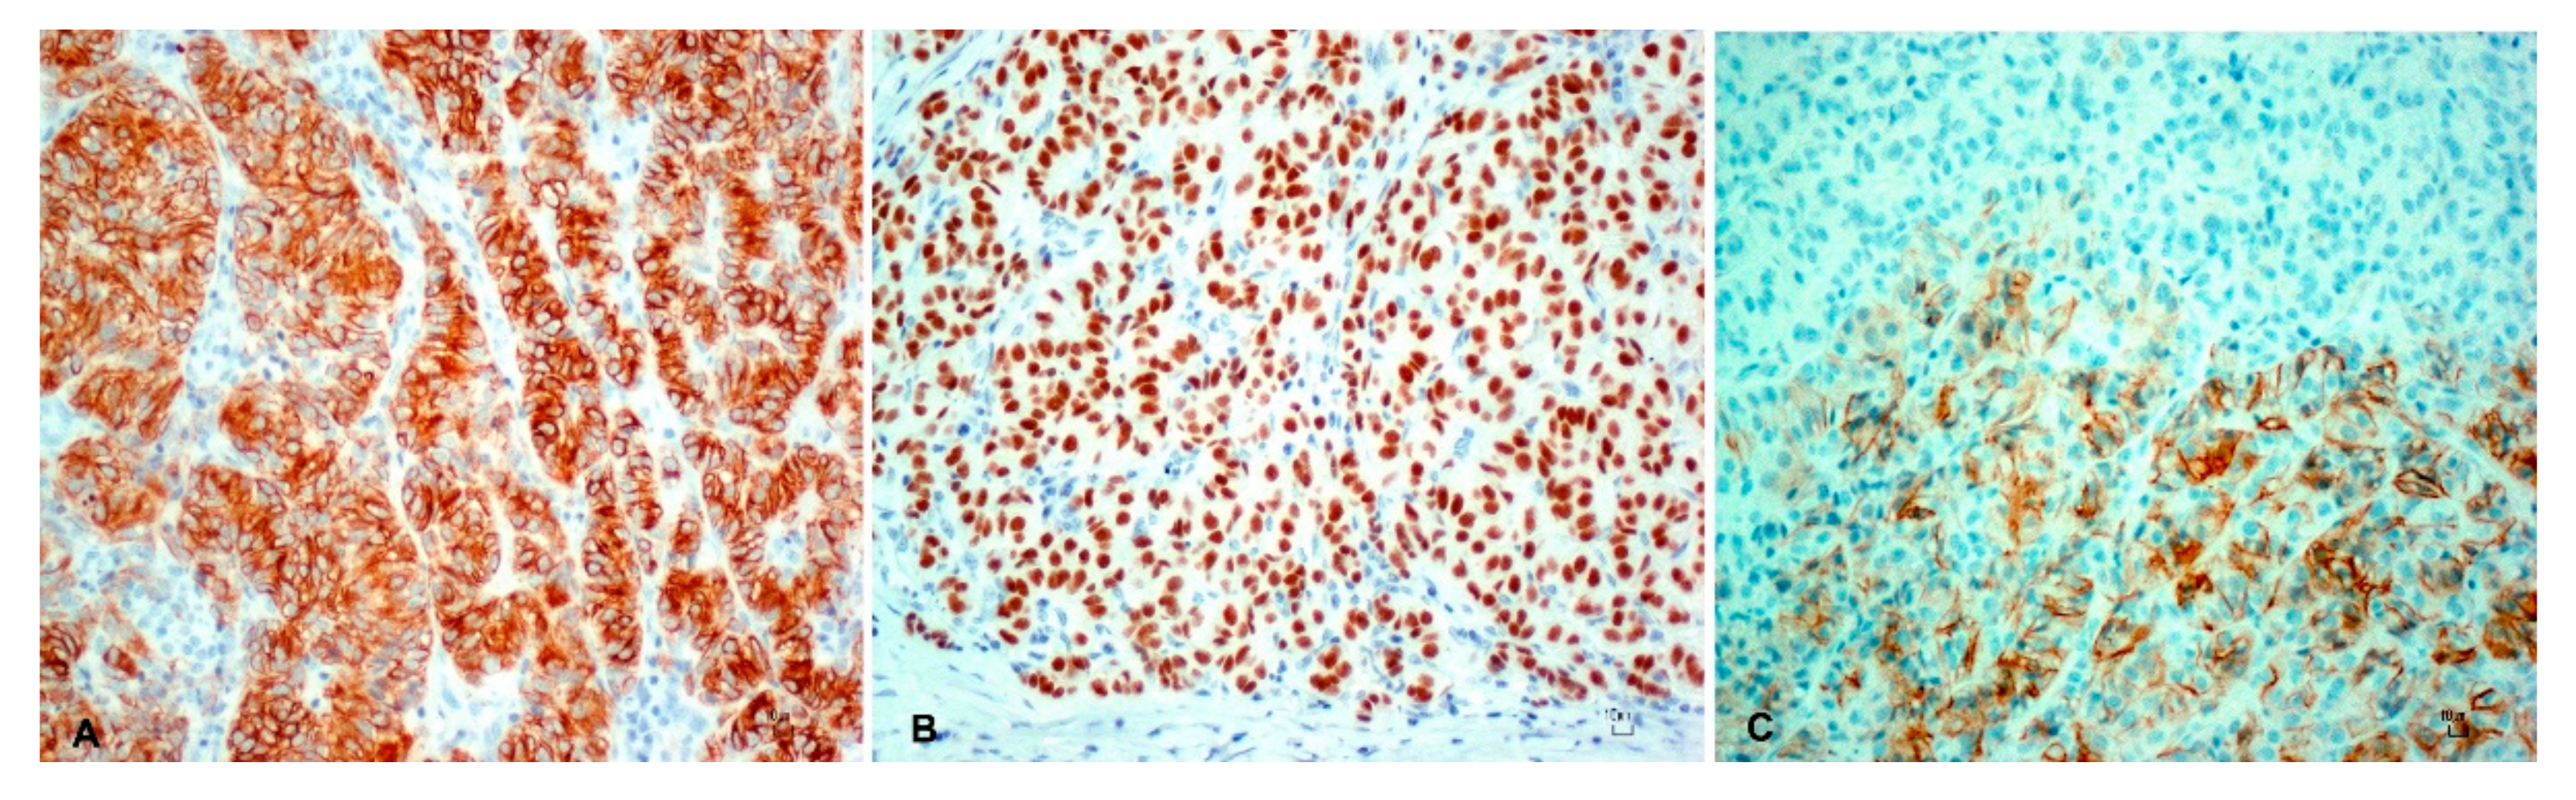

| Tumor | CK AE1/AE3 | CK 34BE12 | CK 5/6 | p63 | KI-67 | CD56 | Melan-A |

|---|---|---|---|---|---|---|---|

| Trichoblastoma | ++ | ++ | ++ | ++ | + | + | − |